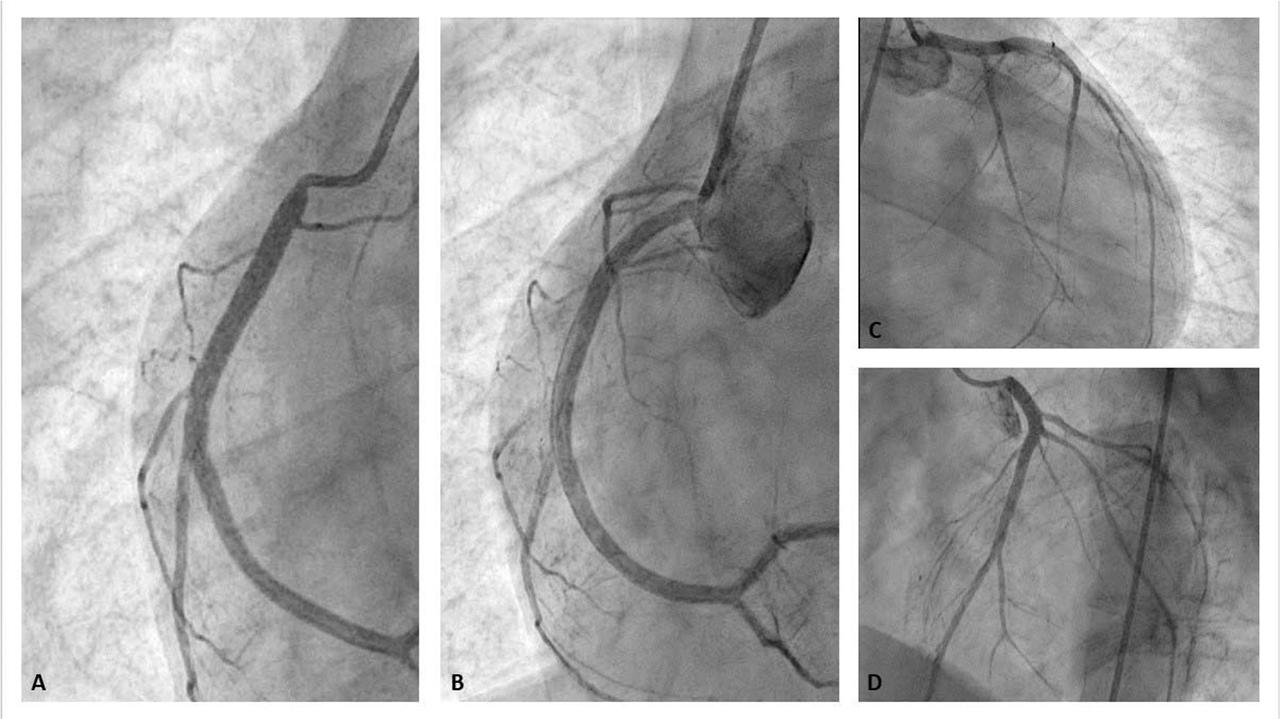

Figure 1